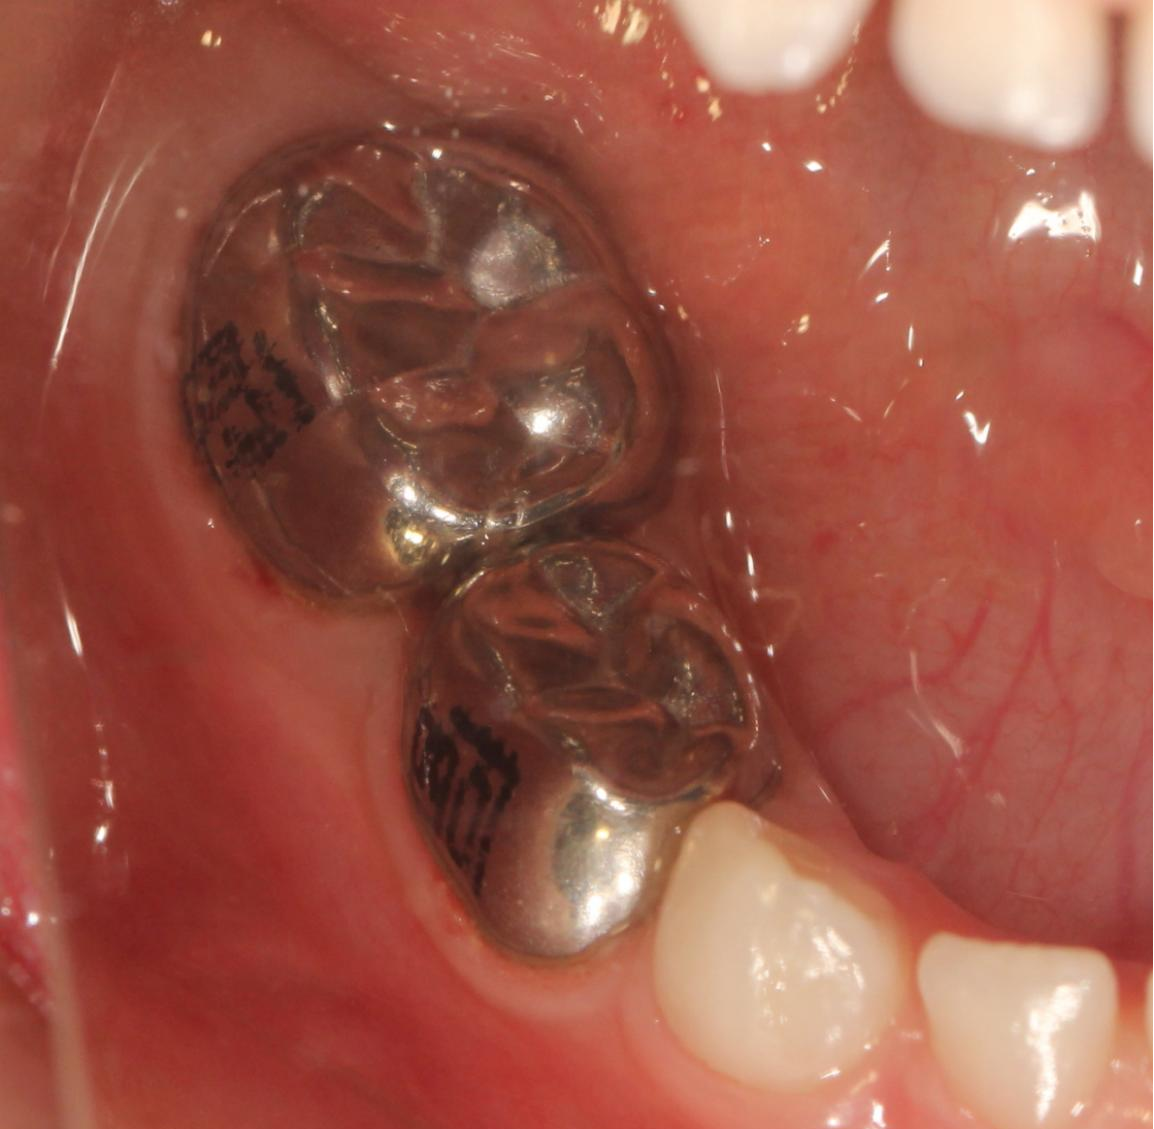

金屬預(yù)成冠由不銹鋼材料制成,它是一種預(yù)成型的、具有乳磨牙牙冠形態(tài)的修復(fù)體,臨床上根據(jù)牙體的大小選用合適的型號,可以恢復(fù)乳磨牙的形態(tài)和咀嚼功能。

研究表明,金屬預(yù)成冠可以使用較長時間,由于其全覆蓋與持久耐用的特點,可以恢復(fù)齲壞牙的外形并防止患牙進一步損害,尤其適用于高患齲風(fēng)險兒童。戴預(yù)成冠之前要去除牙齒齲壞的部分,對乳牙外形進行適當?shù)恼{(diào)磨。